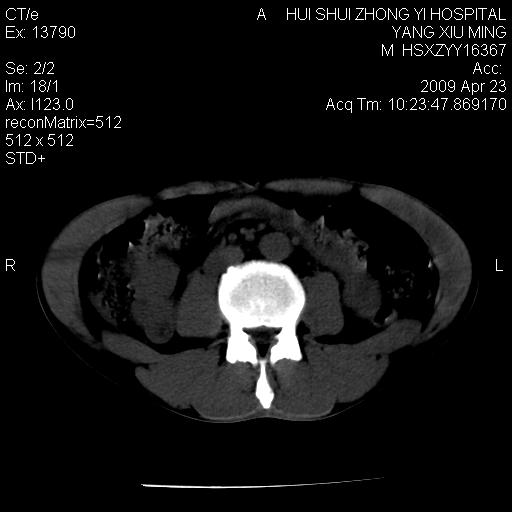

上腹部疼痛一月,呕吐10天,发现左侧颈部包快10天 胸部cr片未见明显异常。

腹膜后淋巴结增大,转移、淋巴瘤?胰腺增大,胰腺炎?占位?颈部考虑增大淋巴结。建议腹部增强扫描。

黑!广泛淋巴结肿大不符合胰腺癌转移。胰腺周围淋巴结肿大致使胰腺看起来大。考虑淋巴瘤可能大。

颈部及腹膜后淋巴瘤可能性大